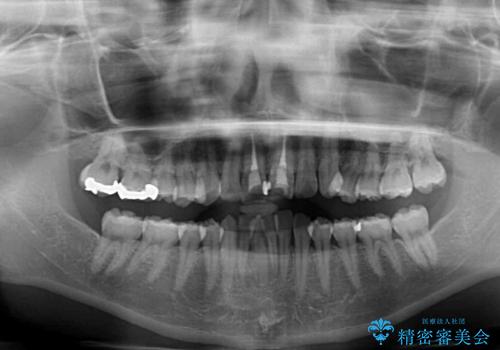

- 前歯の著しい叢生と前突感を気にして来院された患者様です。

叢生が強いため、事前に前歯をワイヤー矯正で速やかに叢生を解消し、その後はインビザラインにて矯正治療を行うこととしました。

ワイヤー矯正を併用したことで前歯の叢生を速やかに解消することができました。

一方口元の突出感を改善するために時間がかかり、2年超を要しましたが、満足のいく仕上がりとなりました。